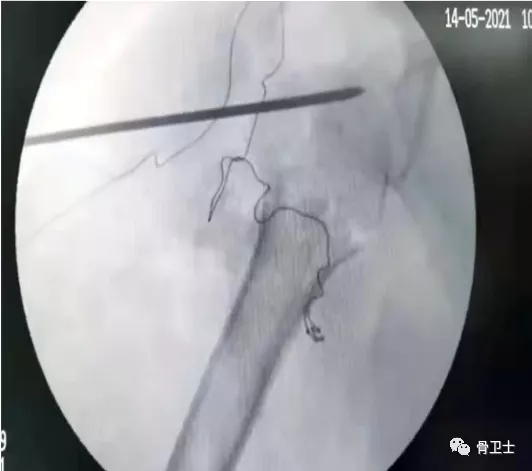

诊断:右肱骨近端骨折(Neer分型3部分骨折);老年性骨质疏松症;轻度贫血;高血压病。治疗方法:入院后于5月14日,在全麻下行右肱骨近端骨折髓内钉内固定术。胡立冬主任指出,此患者具有手术指征,针对此类患者也有几种不同的手术方案,如钢板固定、髓内钉固定和关节置换。选择手术方式要根据患者的实际情况,因为患者有骨质疏松,如果采用钢板固定,肱骨头把持力度不够;如果采用关节置换,手术时间短,出血量大,伤口大,术后患者疼痛比较严重,置换时假体放置的时机、位置非常重要;髓内钉固定创伤小、手术时间短,更符合生物力学的要求,髓内钉系统属于轴心固定,应力遮挡效应较小,骨膜剥离少,神经血管损伤的可能性小,患者术后康复良好。

▲术中影像